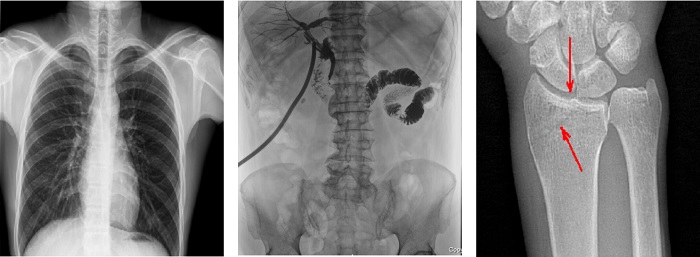

搭載100μm高品質(zhì)動態(tài)平板探測器的普利德多功能懸吊動態(tài)DR,不僅滿足常規(guī)的數(shù)字化X線全身攝影需求,同時(shí)還擁有數(shù)字?jǐn)z影、數(shù)字透視、數(shù)字造影、全景拼接等多種功能,極大地拓展了X線檢查在臨床應(yīng)用范圍,為醫(yī)院臨床應(yīng)用帶來更多實(shí)用價(jià)值?;诎傥⑵桨宓母咔宄上?,圖像清晰度與分辨率更高,可滿足不同檢查部位對細(xì)節(jié)成像的高品質(zhì)要求,在胸腹部、脊柱等復(fù)雜骨骼和軟組織的攝片上應(yīng)用,更便于觀察隱匿性病灶,精準(zhǔn)識別疑難病癥。

不同于靜態(tài)DR拍攝隱匿性病灶時(shí),由于組織重疊病灶難辨,耗費(fèi)時(shí)間更長且易漏診、誤診,普利德多功能懸吊動態(tài)DR可通過動態(tài)實(shí)時(shí)連續(xù)成像,對于重疊部位病灶或者易被遮擋的病灶進(jìn)行多角度動態(tài)觀察,毫秒級時(shí)間內(nèi)實(shí)現(xiàn)動靜態(tài)轉(zhuǎn)換點(diǎn)片,快速、精準(zhǔn)完成攝片。比如隱匿性肋骨骨折,可在透視下觀察患者的呼、吸過程,避開重疊影像,快速點(diǎn)片,保證檢查部位的病癥不被遺漏,實(shí)現(xiàn)精準(zhǔn)診斷。